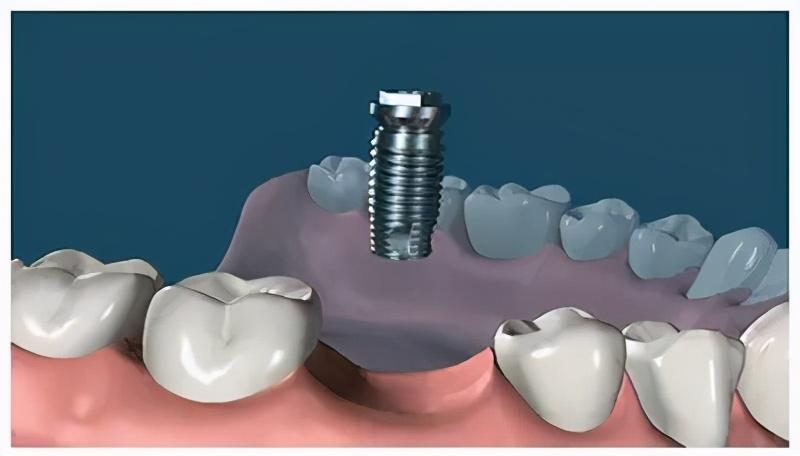

種植牙,全稱為人工種植牙,分成三個(gè)部分:種植體(人工牙根)、基臺(連接體)和牙冠(牙齒)。

種植體是一種高度精密的螺絲構(gòu)造,它外部的螺紋和微表面結(jié)構(gòu)與牙床骨接觸,引導(dǎo)牙床骨細(xì)胞生長到種植體表面,以達(dá)到種植體與牙床骨充分結(jié)合,增強(qiáng)其咀嚼力量及穩(wěn)定性能的目的。

確定能手術(shù)后,才會診斷取模、制定種植牙方案。(第一次大約1個(gè)多小時(shí))然后正式開始種植牙手術(shù)。在牙槽骨上制備一個(gè)孔,植入人工種植體。將牙骨床內(nèi)嚴(yán)密縫合,大約一個(gè)星期后可以拆線(這次大概7--10天)。

注明:此植體只是模擬位置,不做確切種植位置。